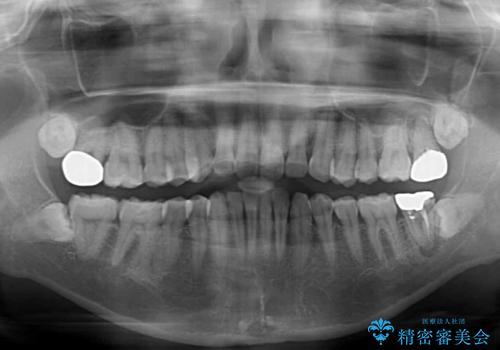

- 上下前歯や奥歯の虫歯治療を希望して来院された患者様です。

全顎的にむし歯が多く、根管治療の必要奥歯や、審美的に気になっている前歯を中心にオールセラミッククラウンにて補綴治療を行うこととしました。

上顎前歯は歯肉退縮により歯根が露出していたため、事前に歯肉移植術により根面被覆を行い、その後にオールセラミッククラウンを装着することとしました。